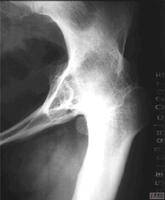

1.病理学:不规则的软骨损害,在负重区域的软骨下骨硬化、囊肿,边缘骨赘增生,干骺端血流增加及不同程度的滑膜炎。

2.组织学:早期软骨表面碎裂、软骨细胞增生、软骨面纵向裂开、结晶沉积,同时存在着软骨修复、骨赘增生;晚期出现软骨的彻底破坏,表现为软骨硬化、软骨消失及软骨下局灶性骨坏死。

3.生物力学:关节软骨的可伸张性、抗压力、抗剪切力及软骨通透性降低。软骨水分增加,过度肿胀,软骨下骨硬化。

1.关节软骨:正常的膝关节软骨为光滑的蓝白色,边缘规则、整齐。膝关节骨质增生早期关节软骨发生软化、失去弹性和光泽,颜色浅黄,活动时发生磨损,软骨发生碎裂、剥脱,致使软骨下骨外露,磨损小的外周软骨面出现增殖和肥厚,通过软骨内化骨而形成骨赘。

2.软骨下骨:磨损较大的中央部分软骨下骨发生象牙质变,骨质密度增加而硬化,外围承受应力较小,软骨下骨发生萎缩,出现囊腔样病变。